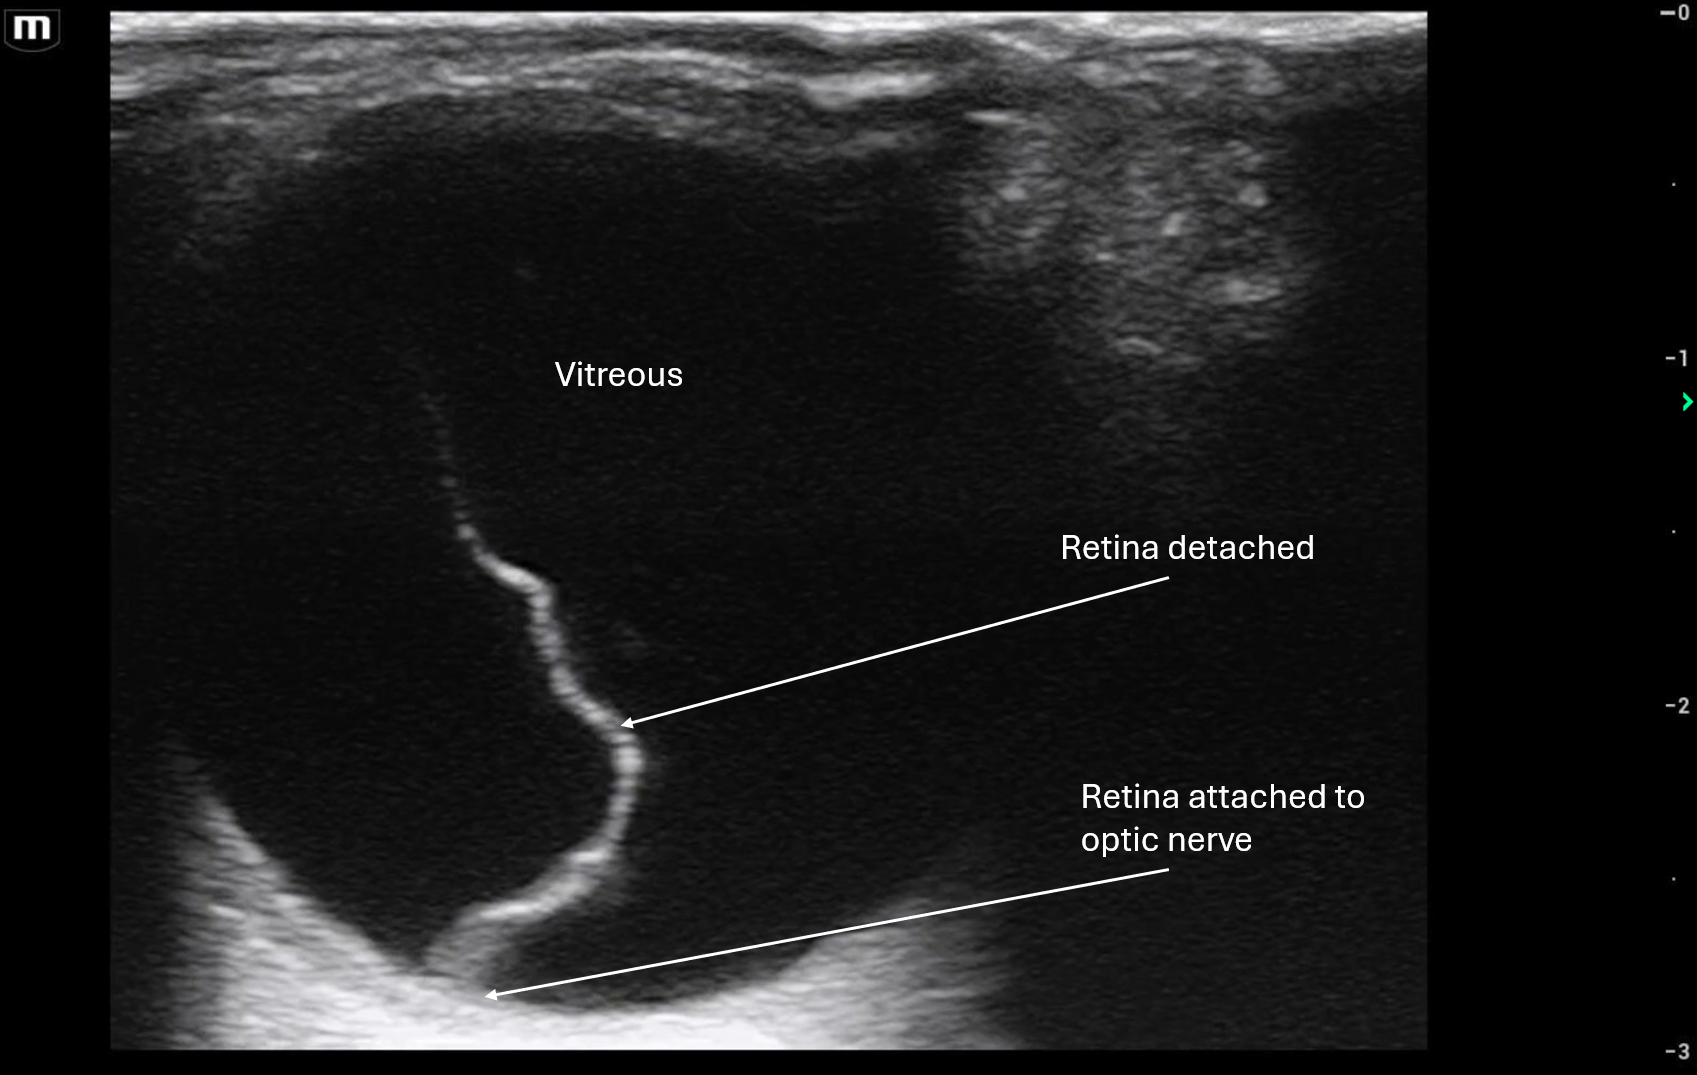

In Clip 1 there is a thick bright hyperechoic line that extends from the optic disc, very much tethered to the back of the eye ball, that is the retina that has detached from the back of the eye.

In Clip 2 it shows that the retina does seem attached to the optic disc because you can see the optic nerve sheath in this image.

In both clips you can see that when the patient moves his eye, the retina is mobile but attached to the optic disc/back of the eye. This is concerning for retinal detachment until proven otherwise!

• Hyperechoic, thick linear membrane within the vitreous

• Tethered to the optic disc (key distinguishing feature)

• V-shaped, Y-shaped, or funnel-shaped configuration in larger detachments

• Limited mobility with eye movement (moves less than vitreous debris)

• Often described as a “sail” or “curtain” floating in the posterior chamber